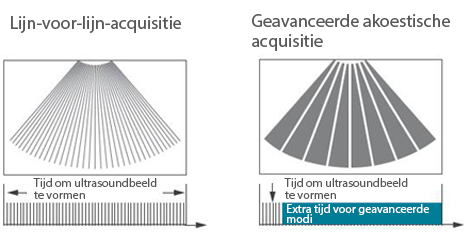

Sinds de oprichting van het bedrijf is Mindray voortdurend op zoek naar nieuwe manieren om het diagnostisch vertrouwen te vergroten. Resona 7 wordt aangestuurd door de meest revolutionaire ZONE Sonography?-technologie. Zijn nieuwe ZST+-tilt de kwaliteit van ultrasoundbeeldvorming naar een hoger niveau door middel van zoneacquisitie en kanaalgegevensverwerking.

Naast de hoogwaardige beeldvormingskwaliteit verbetert de Resona 7 tevens de klinische onderzoeksmogelijkheden met de revolutionaire V Flow voor vasculaire hemodynamische evaluatie, en de intelligentste vlakacquisitie van een 3D-gegevenssets voor de diagnose van het foetale, centrale zenuwstelsel. Met zijn combinatie van de meest intu?tieve, op vingerbewegingen gebaseerde multi-aanrakingsbediening en alle essenti?le klinische functies loopt de Resona 7 voorop in de nieuwe golven van ultrasoundinnovatie.